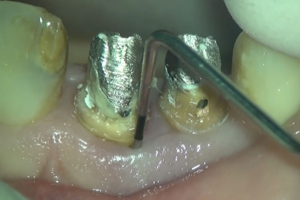

マイクロスコープを使用することで、根管の入り口や、隠れた管、さらには過去の治療で取り残された充填剤などを視認しながら除去できます。

精密根管治療

精密な清掃

感染した組織(細菌)をできる限り取り除き、再発のリスクを軽減することを目指します。

破折の診断

肉眼では判別が難しい、歯の根の微細なヒビ(破折)も、拡大視野であれば早期に発見できる可能性が高まります。